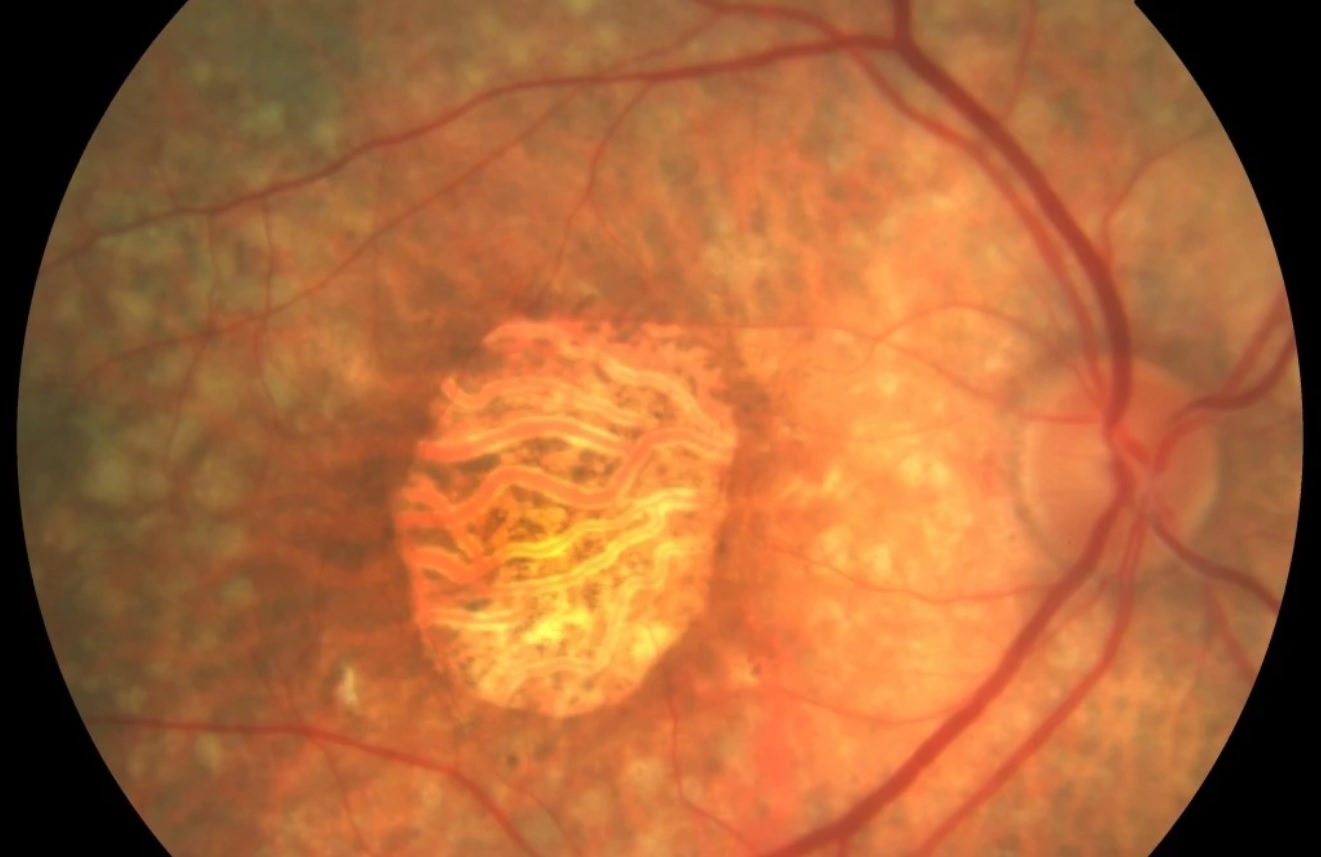

Quais são achados típicos no exame fundoscópico que sugerem DMRI Exsudativa?

Extravasamento (exsudatos, edenma macular)

Hemorragias

Cicatriz disciforme

A presença concomitante de fibroblastos, pode levar a fibrose local, após regressão deses vasos, formando uma área extensa de fibrose sub-retiniana conhedida cono Cicatriz Disciforme.